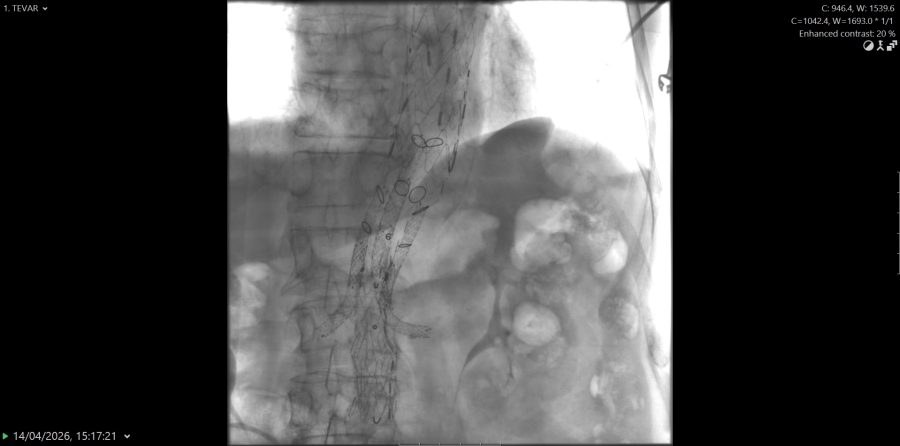

„Ovakvi zahvati predstavljaju vrhunac suvremene endovaskularne medicine i zahtijevaju iznimnu koordinaciju multidisciplinarnog tima koji uključuje interventne radiologe, kardiokirurge, vaskularne kirurge, anesteziologe, inženjere radiologije, instrumentarke i anestezičare. Tijekom zahvata ugrađena su ukupno tri stenta duž aorte, od arterije subklavije do bifurkacije aorte. Kako bi se osigurala adekvatna prokrvljenost vitalnih organa, postavljen je posebno dizajniran stent s otvorima za bubrežne arterije te arterije koje opskrbljuju crijeva“, pojasnio je dr. Gojko Bogdan, voditelj Kliničkog odjela za vaskularnu i intervencijsku radiologiju te dodao se pacijent nakon zahvata osjeća odlično.